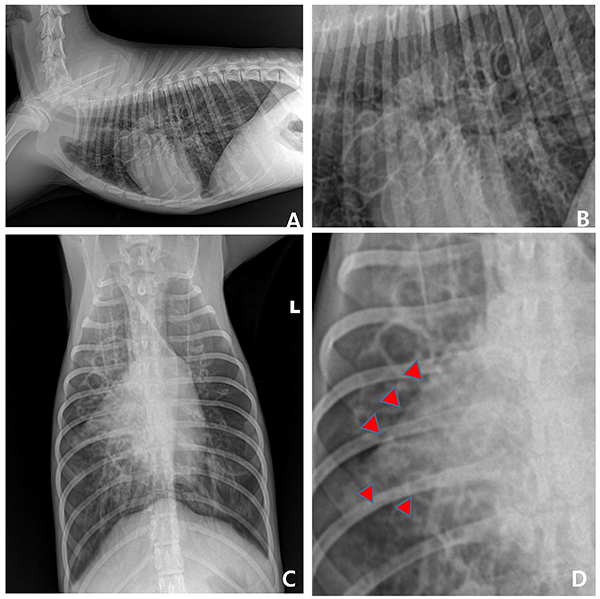

퇴원 이후에도 지속적인 투약과 2주 간격의 모니터링을 진행하였다.그러나 3개월이 지났을 때 다시 호흡기 증상이 재발하였고, 일반 방사선 상에서 폐간질 침윤과 심한 기관지 침윤이 재발한 것을 알 수 있었다[그림 3].

재입원하여 동일한 방법으로 치료를 진행하였고, 1개월 정도 지나서 전산화 단층 촬영을 하였다[그림 4]. 폐엽 전반에 걸쳐 기관지의 tapering이 소실되고 원통형으로 확장되어 있는 것을 확인할 수 있었으며, 우측 전엽 배쪽(ventral) 부위에는 국소적으로 포도송이 모양의(“grape cluster” appearance) 주머니형 기관지 확장증도 동반되어 있었다.

또한 확장된 기관지 벽은 전반적으로 비후되어 있었으며, 여러 폐야에서 다양한 영역을 보이며 간질침윤이 확인되었다.